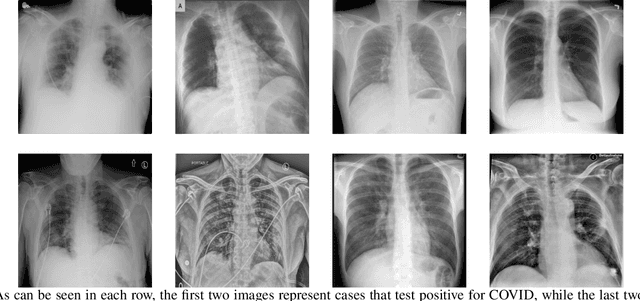

Abstract:This paper introduces a groundbreaking classification model called the Controllable Ensemble Transformer and CNN (CETC) for the analysis of medical images. The CETC model combines the powerful capabilities of convolutional neural networks (CNNs) and transformers to effectively capture both local and global features present in medical images. The model architecture comprises three main components: a convolutional encoder block (CEB), a transposed-convolutional decoder block (TDB), and a transformer classification block (TCB). The CEB is responsible for capturing multi-local features at different scales and draws upon components from VGGNet, ResNet, and MobileNet as backbones. By leveraging this combination, the CEB is able to effectively detect and encode local features. The TDB, on the other hand, consists of sub-decoders that decode and sum the captured features using ensemble coefficients. This enables the model to efficiently integrate the information from multiple scales. Finally, the TCB utilizes the SwT backbone and a specially designed prediction head to capture global features, ensuring a comprehensive understanding of the entire image. The paper provides detailed information on the experimental setup and implementation, including the use of transfer learning, data preprocessing techniques, and training settings. The CETC model is trained and evaluated using two publicly available COVID-19 datasets. Remarkably, the model outperforms existing state-of-the-art models across various evaluation metrics. The experimental results clearly demonstrate the superiority of the CETC model, emphasizing its potential for accurately and efficiently analyzing medical images.